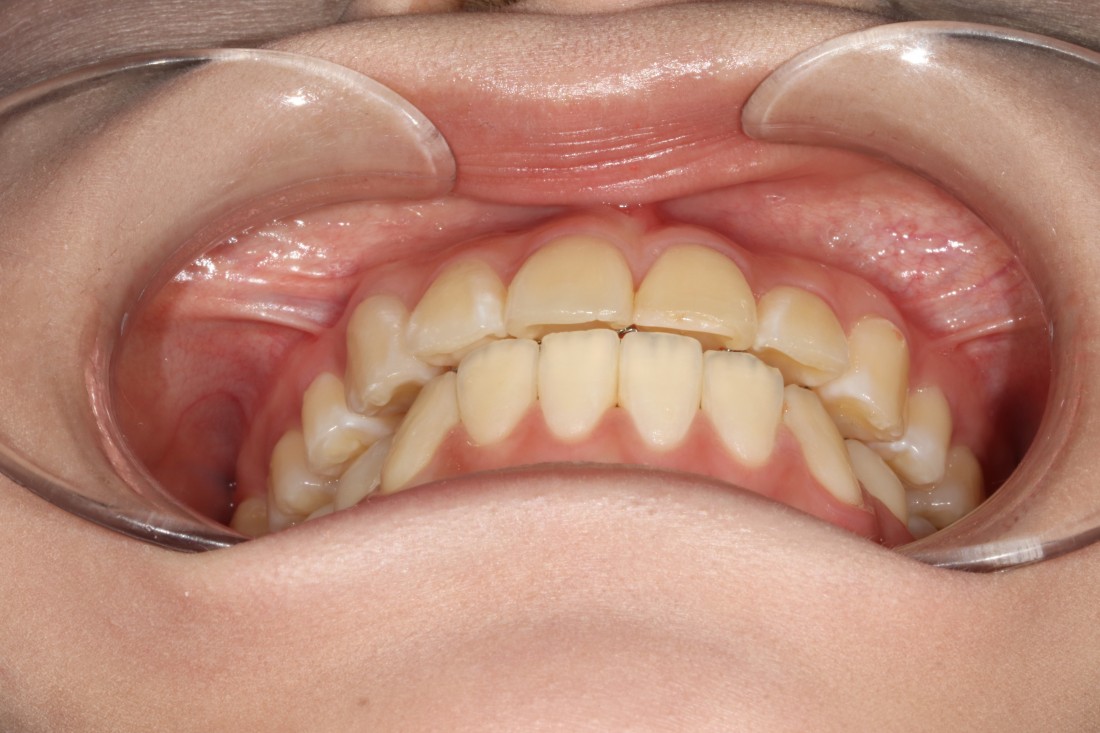

수완동 교정치과를 선택할 때는

교정전문의가 경험이 풍부한지,

교정전문의가 상담부터 진료 후 관리까지

책임지고 진료하는 곳인지

꼼꼼하게 따져보는 것이 중요합니다.

서울우리아이치과는

20년 이상 교정진료만을 담당해오신

교정전문의 대표원장님께서

교정진료의 시작부터 끝까지

1:1 책임진료를 통하여

성공적인 치아교정을 완성하고 있습니다.